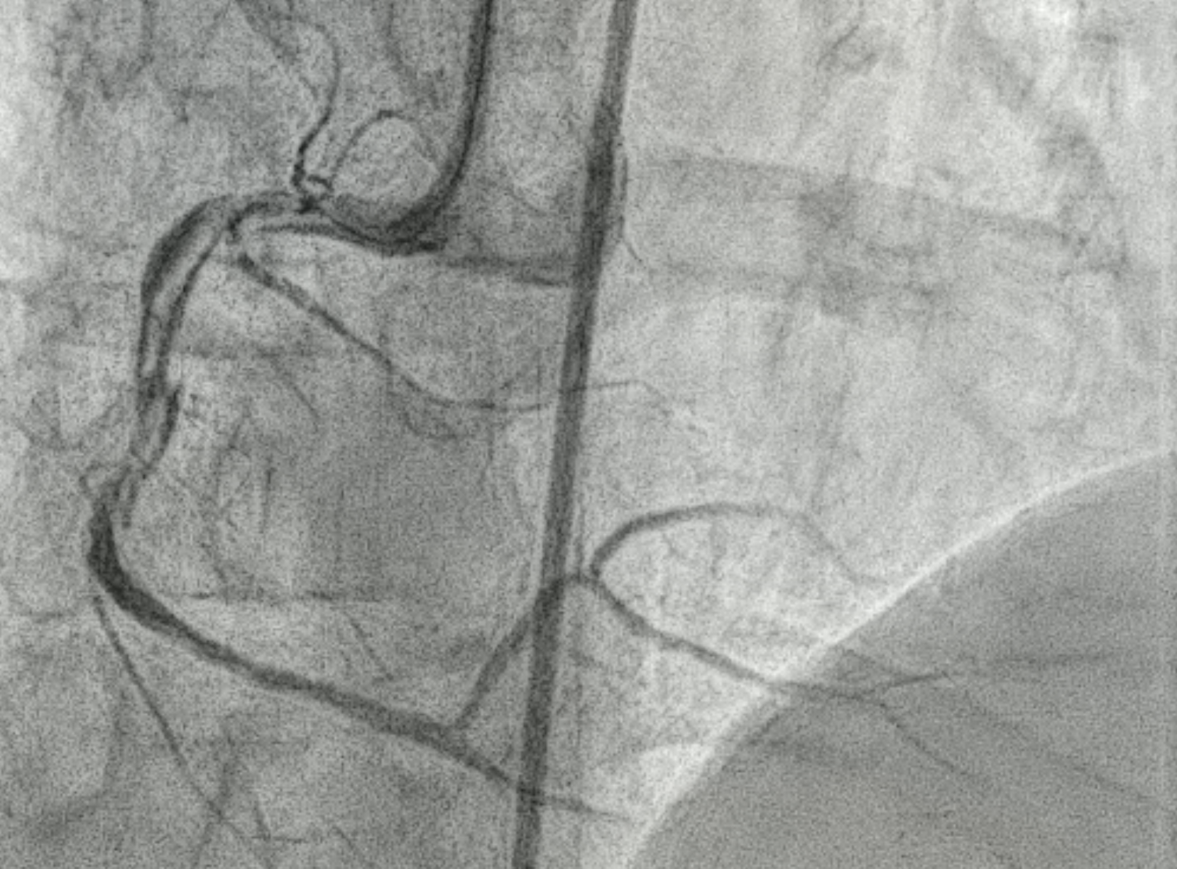

After explaining to the patient, she refused CABG and decided for PCI. 6F SAL1 as guiding catheter, starting intervention from RCA. Pressure damping was noted after engagement. While wiring Fielder FC to RCA, extravasation occurred followed by hypotension, bradycardia and nausea.IV saline challenge, inotropics agent were prescribed to stablelize the patient. Echogram showed no tamponade.

The SAL1 guiding catheter was unstable, jumping in and out the ostium. We deployed PK Papyrus 2.5 x 20 mm stent graft to dRCA quickly and planned to deployed another DES to p-dRCA. However, the patient agitated and the whole system was removed, leaving severe spiral dissection, starting from the ostium to middle RCA.We tried to wire FC, XTA and sion balck to true lumen but fail. Switched to 6F JR guiding but still fail.We wired FC to distal RCA with parallel wire technique and checked IVUS. The distal wire was over true lumen, but false lumen wiring was noted since proximal RCA.We wired XTA to true lumen under IVUS image. Then true lumen wiring was completed.We dilated with 1.5 balloon. Followed by Ryurei 2.50 x 15 mm to mRCA.We deployed Ultimaster Tansei 3.00 x 38 mm and Ultimaster Tansei 4.00 x 18 mm to p-dRCA.Post-dilated with 3.0, 3.5, and 4.0 NC balloon to RCA.The final IVUS showed well stent expansion.The final flow is good. We closed the procedure smoothly.